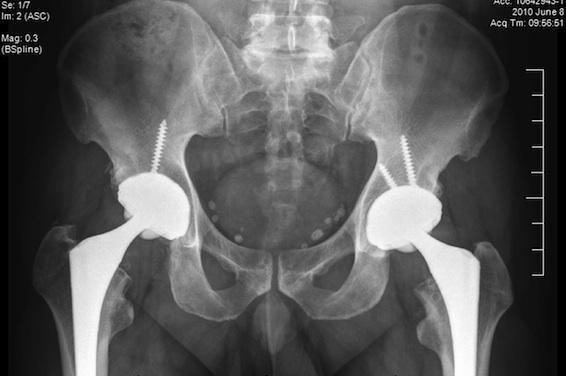

Depuis plusieurs années, les prothèses de hanches métalliques sont pointées du doigt outre-Antlantique et chez nos voisins britanniques. Alors qu’elles sont interdites aux Etats-Unis depuis 2010, la France conseille aux chirurgiens orthopédistes d’éviter leur utilisation « chez les femmes en âge de procréer et les patients allergiques à des métaux ». Une recommandation qui concerne tous les types de prothèses de hanche métallique.

La cause de cette mise en garde ? L’usure anormale de ces prothèses entraînant la libération d’ions métalliques dans la circulation sanguine. C’est justement ce qui s’est produit pour le patient marseillais, Frédéric Simon, implanté en 2010, dont les taux sanguins de cobalt étaient « quatre fois supérieurs à la dose maximale admise », raconte-il dans Le Parisien du mercredi 15 avril. Or, une intoxication au cobalt peut entraîner des problèmes cardiaques, des troubles de la thyroïde ou des cancers.